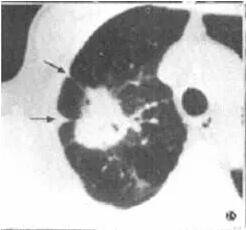

三、毛刺征

肿块边缘不同程度棘状或毛刺样突起,仅见于肿块和肺实质交界面。一般而言,周围型肺癌的毛刺为短毛刺,而结核瘤、慢性炎症的长而稀疏毛刺称长毛刺。